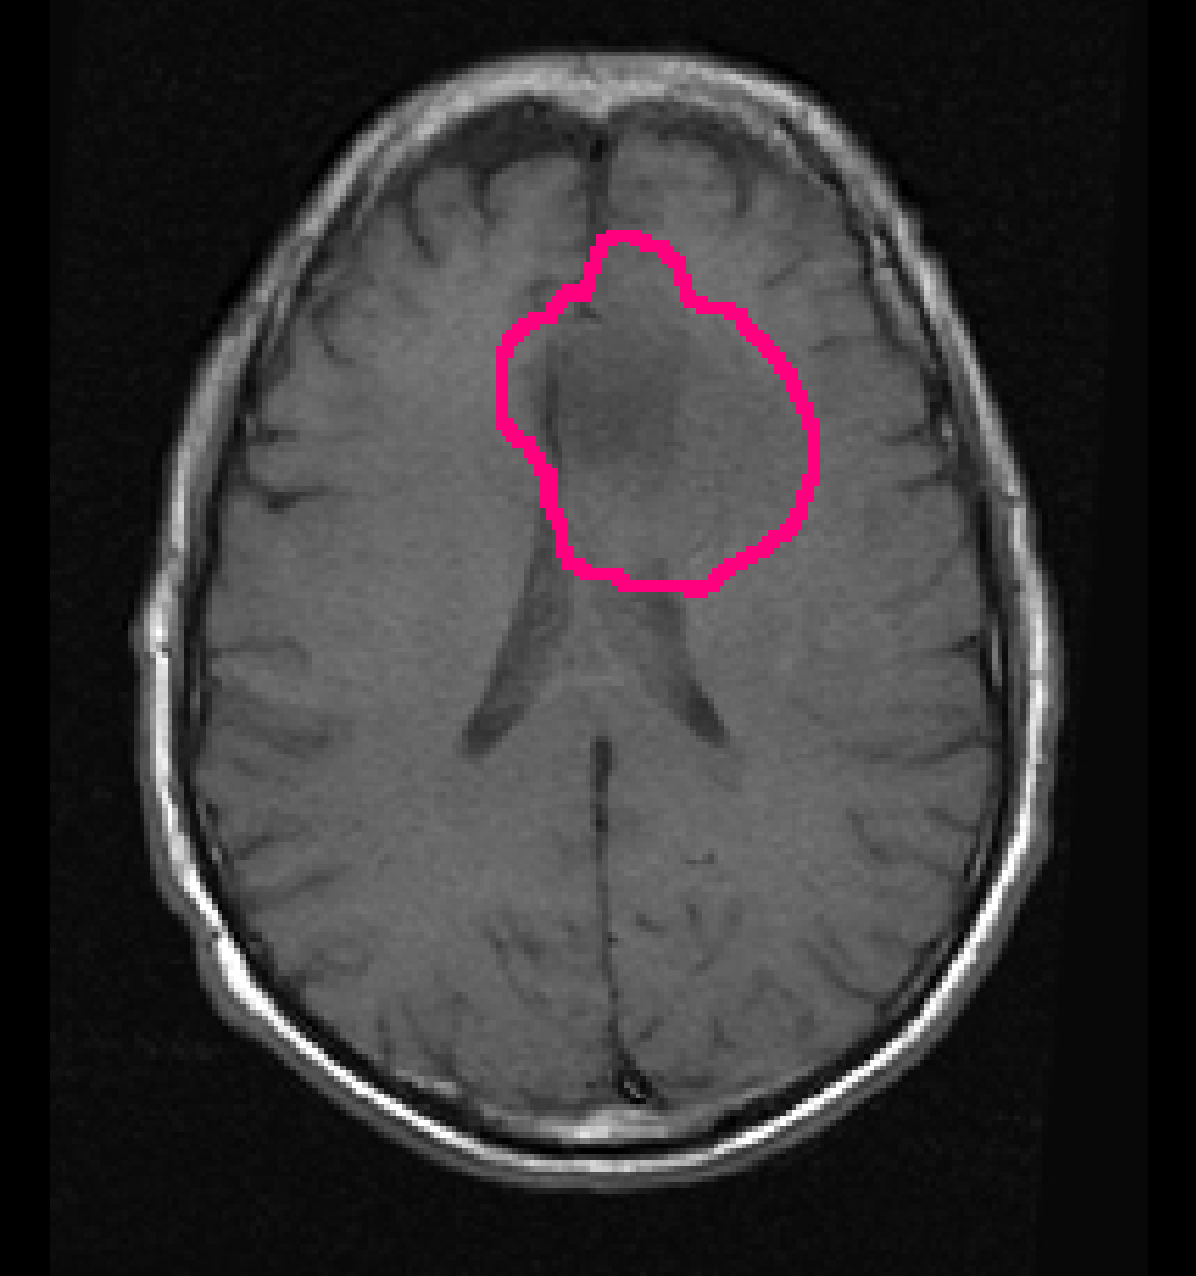

For the automatic segmentation, we achieved a mean DICE score of 0.84, a mean Hausdorff distance of 18.9 mm, and a mean volumetric similarity coefficient of 0.90. Figure 4 shows boxplots of the DICE scores, Hausdorff distances, and volumetric similarity coefficients for the different patients in the test set. In Appendix B we show five patients that were randomly selected from both the TCGA-LGG and TCGA-GBM data collections, to demonstrate the automatic segmentations made by our method.

To demonstrate the automatic segmentations made by our method, we randomly selected five patients from both the TCGA-LGG and the TCGA-GBM dataset. The scans and segmentations of the five patients from the TCGA-LGG dataset and the TCGA-GBM dataset are shown in Figures 12 and 14, respectively. The DICE score, Hausdorff distance, and volumetric similarity coefficient for these patients are given in Table 7. The method seems to mostly focus on the hyperintensities of the T2w-FLAIR scan. Despite the registrations issues that can be seen for the T2w scan in Figure 14(d) the tumor was still properly segmented, demonstrating the robustness of our method.